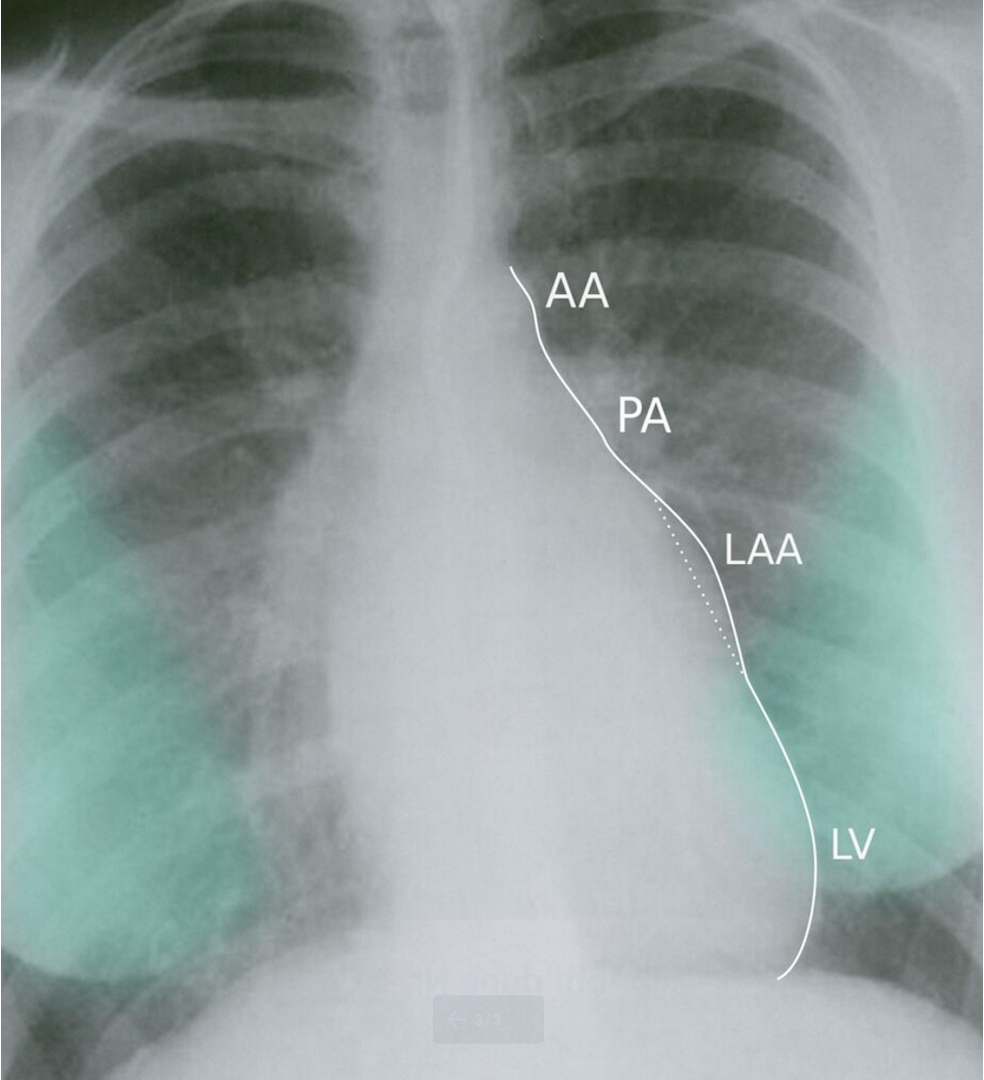

CXR Z

-

Left atrial enlargement

Mitralisation of heart: straightening of left heart border

Elevation of left mainstem bronchus

Evidence of mitral calcification

Evidence of pulmonary edema kerley’s b lines

Double contour of the right border of heart

Imaging

PA view: ⇒ Left atrial enlargement:

- Convexity or straightening of the left atrial appendage.

- Left heart border is straight or convex

- Double density of RTÂ cardiac border

- Elevation of the left main bronchus and splaying of the carina

LA view: posterior protrusion of the upper part of posterior heart border.